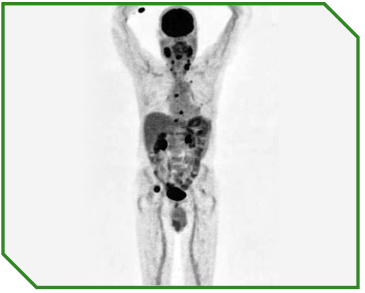

Paciente masculino de 70 anos, previamente hígido, diagnosticado com carcinoma espinocelular de laringe em estágio IVc, com acometimento metastático ósseo e pulmonar ao diagnóstico, ECOG‑PS 1 e expressão de PD‑L1 (CPS 44). O manejo incluiu radioterapia paliativa para controle de dor óssea, seguida de tratamento sistêmico de primeira linha baseado em imunoterapia associada à quimioterapia, com posterior continuidade em esquema de manutenção.